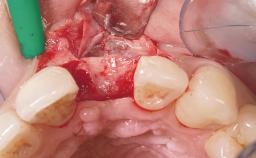

Late Flapless Placement of an Implant in a Maxillary Left Central Incisor Site

Bone Augmentation Horizontal|Staged

Soft Tissue Grafting Simultaneous

Bone Volume Deficient horizontally, requiring prior grafting